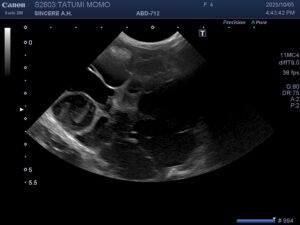

まだ若い猫がコロナウィルスの抗体価が以前高めだったので、今回腹囲が大きくなったと心配して来院されました。触診すると腹水というより両側に固いしこりを触れたので、急いでレントゲンと超音波を取りました。レントゲンでは両腎臓が拡大され、超音波では腎臓実質がハチの巣状の空隙が多数で来ていました。血液検査ではBUNとCREがかなり高くなっています。丁度1年前は正常だったのに、若いから油断したのかもしれませんショックでした。

診断は「多発性嚢胞腎」。これは人でもあるそうですが、猫ではペルシャなどが比較的多いとされる遺伝病で、腎臓に液体を含んだ袋がたくさんできて腎盂を圧迫し、最終的に慢性腎臓病を引き起こす病気です。治療は嚢胞を潰すのは感染のリスクが高く、腎臓病への対症療法が主になってしまいます。まだ4才、何とかならんものかと胸が痛みます。